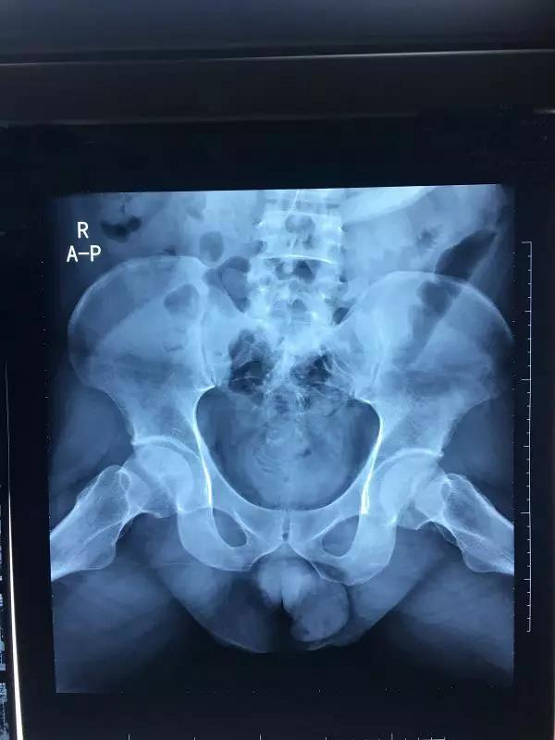

上图为适合汤剂治疗的病例

随着MRI成像的广泛普及,其对坏死组织有了更高分辨率及多平面征象,更好地显示软骨、软骨下骨、骨组织等组织结构受损情况,目前已成为准确诊断股骨头坏死的常用的检查方法以及黄金标准。若早期就被查出股骨头坏死,要尽早配合治疗,优先保髋,避免股骨头置换。